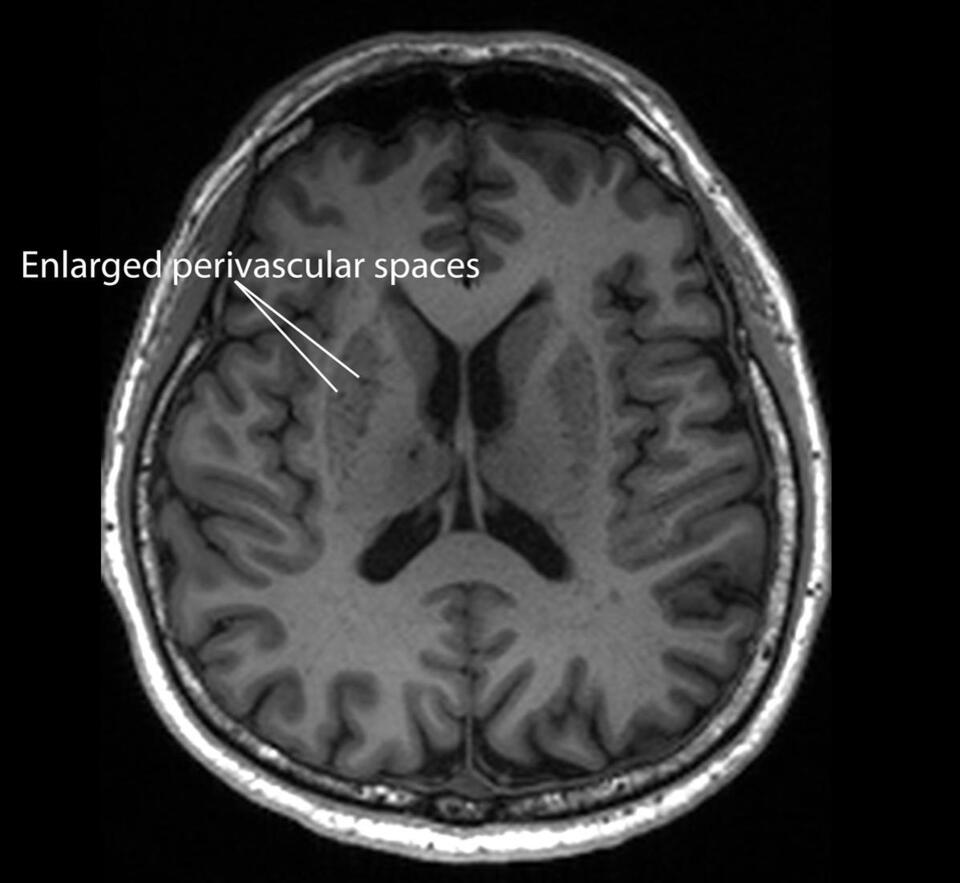

wilsonjames+FollowYour MRI Might Reveal Early Alzheimer’s CluesWild new research says your routine MRI scan could be hiding the earliest signs of Alzheimer’s—way before memory loss kicks in. Scientists found that tiny “clogged drains” in the brain, called enlarged perivascular spaces, show up on regular scans and are linked to Alzheimer’s risk. If doctors start looking for these, we might catch the disease way sooner and slow it down. Imagine finding out years in advance, just from a scan you’d get anyway! #Health #BodyHealth #AlzheimersAwareness10Share